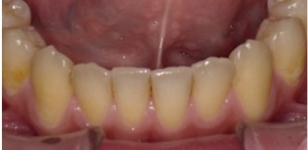

観察方法はPARスコアではなく、もう少しダイレクトな評価になるリトル教授らの方法を使いました。つまり右図のように、後戻りが一番現れやすいと言われている下の前歯において、歯と歯の接触点間の距離をmm単位でデジタル写真上で計測し、それらの合計のミリ数を「指数」とするものです。歯並びが綺麗であれば“0”に近い数字になり、数字が大きいと悪い歯並びを意味します。この写真の歯と歯の接触点間の距離の合計は9.3mmでしたから、指数は9.3になります。